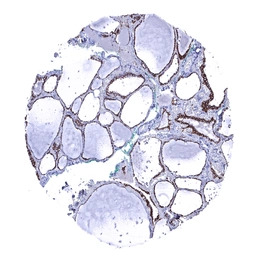

IHC-P analysis of human thyroid gland tissue section using GTX04455 CDH16 antibody [MSVA-516R] HistoMAX.

Strong membranous CDH16 staining of follicle cells CDH16 immunohistochemistry.